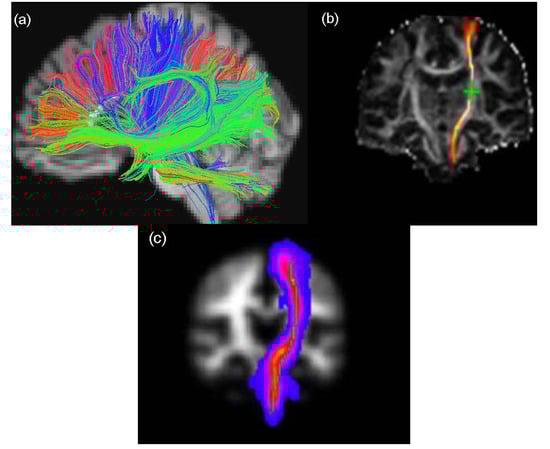

Tractography aims to reconstruct major WM tracts in 3D by piecing together voxel-based estimates of the underlying continuous fibre orientation field starting from an initial seed point [] (Figure 2). Since tractography output can be highly sensitive to the choice of initial seed point placement, a number of different approaches have been suggested to allow the same tract to be identified in different subjects across a population (e.g., Conturo et al., 1999 []; Clayden et al., 2007 []). As discussed below, there are two common types of fibre tracking algorithm that can be employed for tractography analysis, namely deterministic and probabilistic, which differ in the way they deal with multiple fibres within a single voxel.

Figure 2.

Examples of the visualization of WM tractography data. The figure shows (a) whole brain WM overlaid on a high-resolution T1-weighted volume scan produced by TrackViz [], (b) left corticospinal tracts of the same participant (CST) generated using FSL’s BedpostX/ProbTrackX algorithm and (c) maximum intensity projection of a standard space group map of left CST obtained from 90 participants aged over 65 years using TractoR [,].